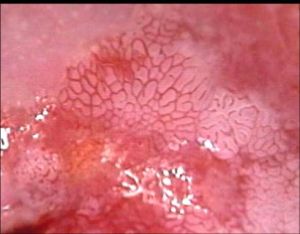

病變特徵非典型增生從基底層開始,逐漸向表層發展,若上皮全層皆為異型細胞所代替,則為 原位癌。將子宮頸上皮非典型增生至原位癌這一系列癌前病變的連續過程統稱為CIN。根據非典型增生的程度和範圍,CIN 分為Ⅰ、Ⅱ、Ⅲ級。

CINⅠ級(輕度非典型增生):異型細胞局限於上皮層的下 1/3 區。

CINⅡ級 (中度非典型增生) :異型細胞占上皮層的 1/2~2/3 ,異型性較 Ⅰ 級明顯。

CINⅢ級(重度非典型增生及原位癌):異型細胞超過上皮層的 2/3 者為重度非典型增生;達全層者為原位癌;異型性較Ⅱ級明顯,核分裂像增多,原位癌可出現病理性核分裂像。